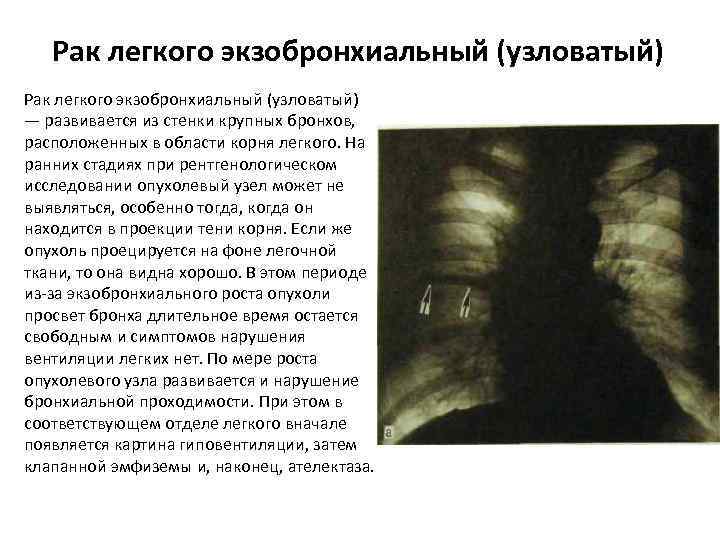

Рак легкого экзобронхиальный (узловатый) — развивается из стенки крупных бронхов, расположенных в области корня легкого. На ранних стадиях при рентгенологическом исследовании опухолевый узел может не выявляться, особенно тогда, когда он находится в проекции тени корня. Если же опухоль проецируется на фоне легочной ткани, то она видна хорошо. В этом периоде из-за экзобронхиального роста опухоли просвет бронха длительное время остается свободным и симптомов нарушения вентиляции легких нет. По мере роста опухолевого узла развивается и нарушение бронхиальной проходимости. При этом в соответствующем отделе легкого вначале появляется картина гиповентиляции, затем клапанной эмфиземы и, наконец, ателектаза.

Рак легкого экзобронхиальный (узловатый) — развивается из стенки крупных бронхов, расположенных в области корня легкого. На ранних стадиях при рентгенологическом исследовании опухолевый узел может не выявляться, особенно тогда, когда он находится в проекции тени корня. Если же опухоль проецируется на фоне легочной ткани, то она видна хорошо. В этом периоде из-за экзобронхиального роста опухоли просвет бронха длительное время остается свободным и симптомов нарушения вентиляции легких нет. По мере роста опухолевого узла развивается и нарушение бронхиальной проходимости. При этом в соответствующем отделе легкого вначале появляется картина гиповентиляции, затем клапанной эмфиземы и, наконец, ателектаза.